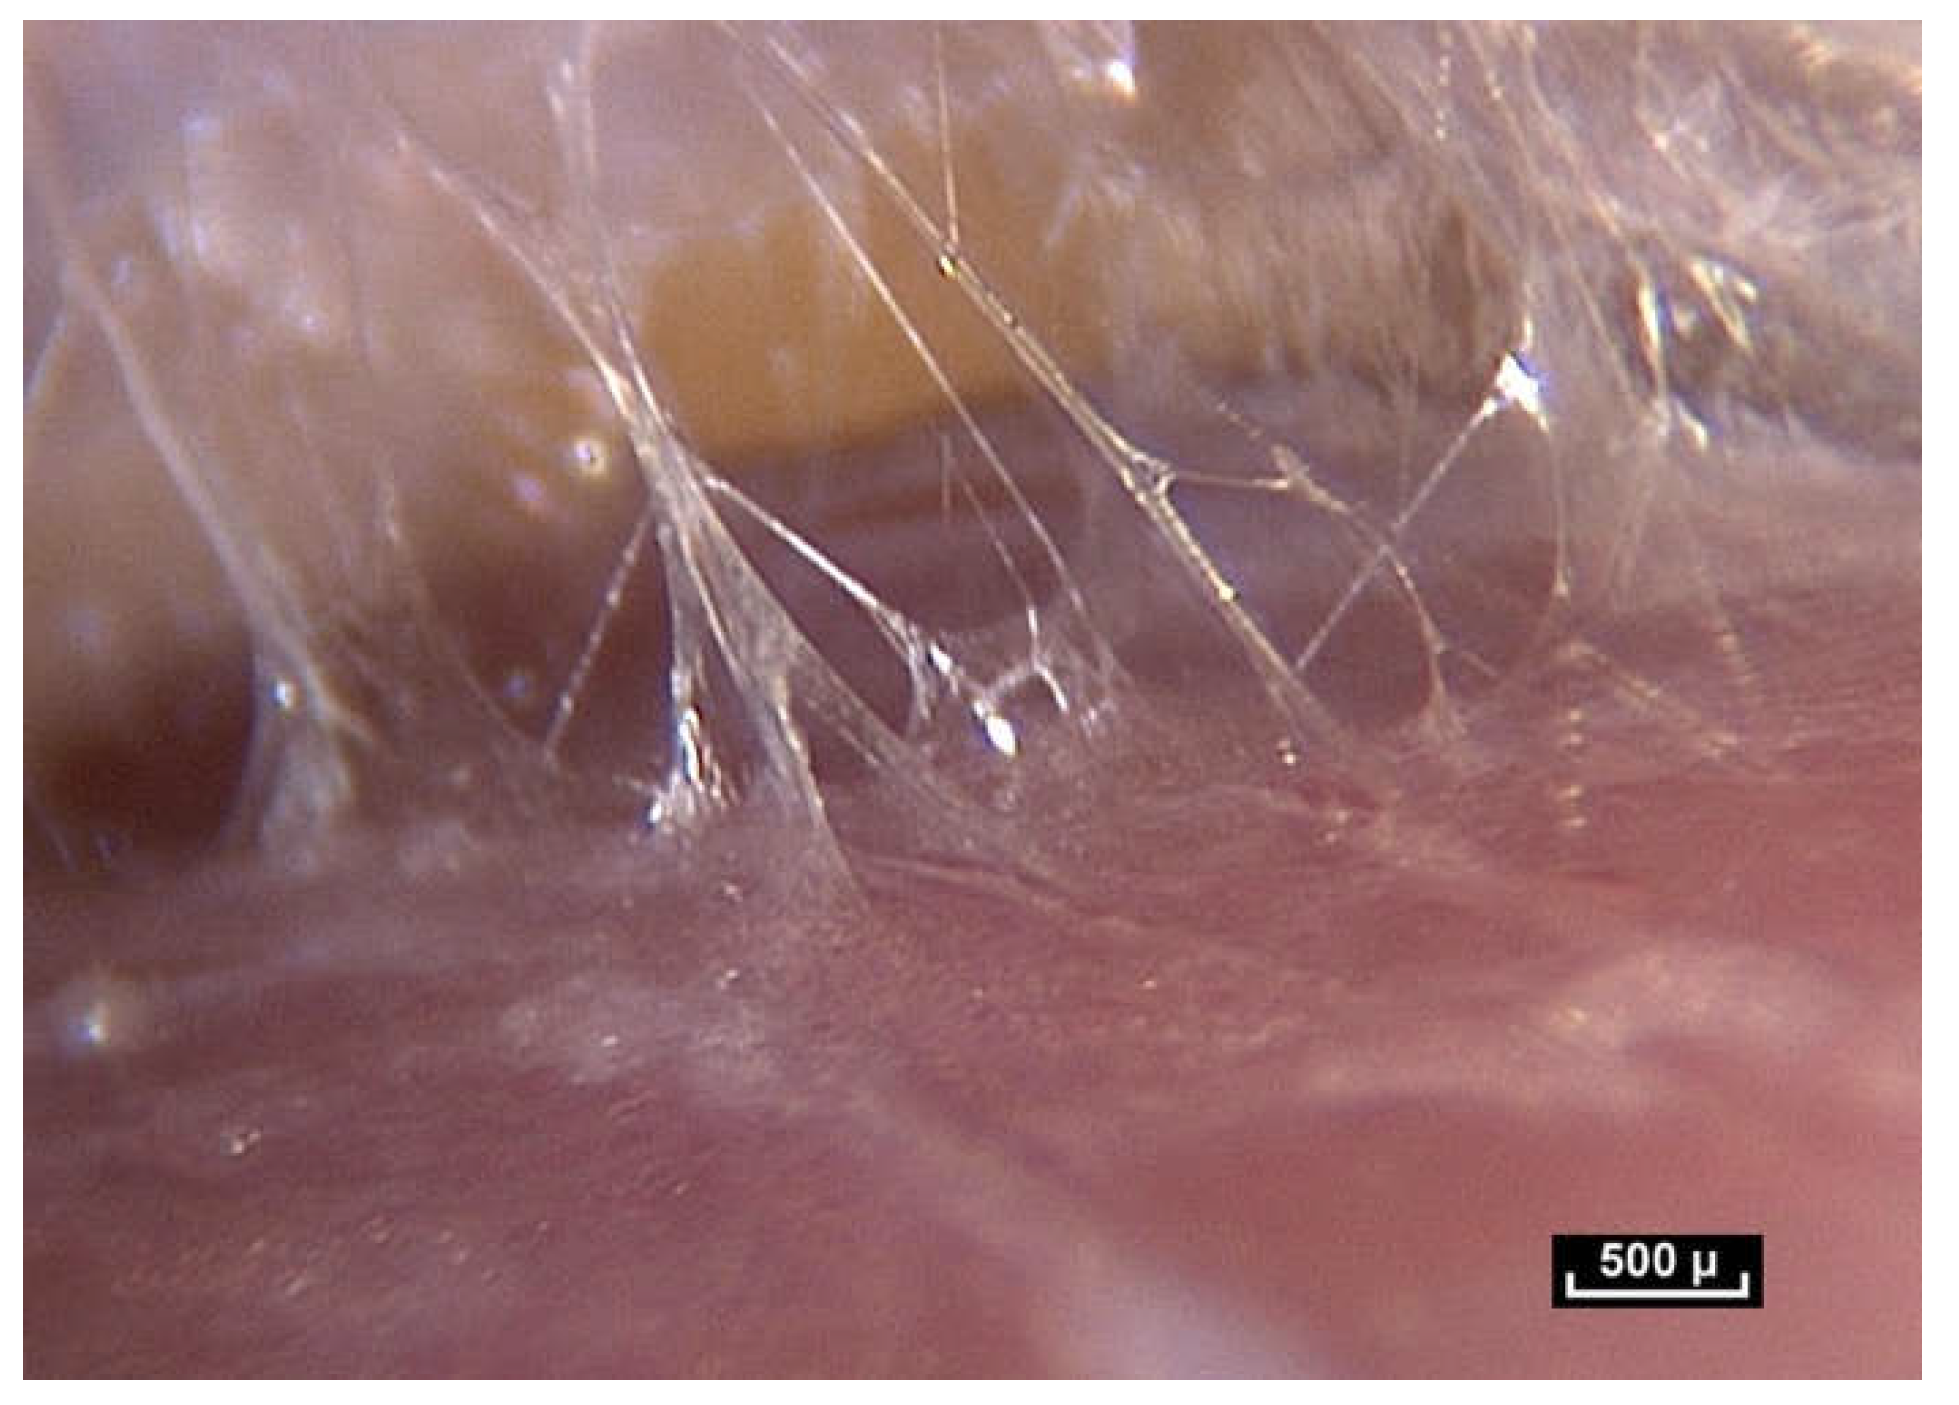

Beneath the “deep fascia” the observable fibrillar continuity extends to the epimysium, which is in continuity with the muscle. The epimysium is also made up of fibers which penetrate into the muscle. There is no visible fibrillar discontinuity, and this area is highly mobile. The area beneath the “deep fascia” appears to be composed of fibers arranged in an irregular manner, and there is no observable discontinuity of the fibers in the fibrillar network from one area to another. The “deep fascia” itself is made of collagen fibers. Its weave is also irregular, an apparently random weave obeying no obvious rules, and yet effective. Here again, the association of an apparent disorder and efficiency can be observed (Figure 5).

Figure 5. (Video S5) (×10 magnification) Muscular aponeurosis are simply densified areas of the same fibrillar network. However, their structure is in an irregular pattern and is different because of their different functional roles.